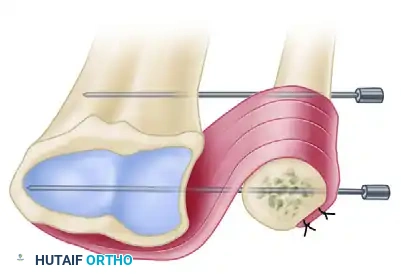

Figure 3: The pronator quadratus is mobilized and transferred to stabilize the distal ulnar stump, often secured with temporary K-wire fixation to maintain the radioulnar interval during healing.

Step 4: ECU Tenodesis and Sling Creation

- Formal Tenodesis Technique: Alternatively, a distally based strip of the ECU tendon (approximately half its width) is harvested.

- Drill a transverse hole through the distal ulnar stump.

- Pass the harvested ECU tendon strip through the drill hole in the ulna.

- Tension the tendon strip with the forearm in neutral rotation and the wrist in slight extension. Suture the tendon back onto itself or to the adjacent periosteum using non-absorbable braided sutures (e.g., 2-0 Ethibond or FiberWire). This tenodesis creates a powerful checkrein that retards radioulnar convergence.

Figure 5: Formal ECU tenodesis. A strip of the ECU is passed through a drill hole in the contoured ulnar stump and sutured to itself. Note the temporary transverse K-wires maintaining the radioulnar space.